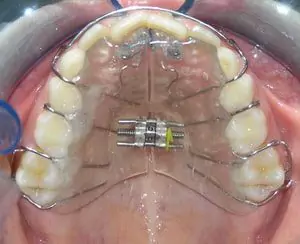

Removable Appliances

These are the appliances which are made of acrylic (tooth-coloured or pink) and can be worn and removed by the patients. These are usually used for minor teeth and jaw corrections. They are very aesthetic and they require to be worn for 24 hours by the patient. These are usually called plates and need activation or supervision by an orthodontist every 1 month or 15 days. At Smilex, a team of best orthodontists in Pune provides you with complete supervision and guidance with regards to your appliances.

Different Types of Removable Appliances

These are the upper and lower plates given together or separately to correct the small or large jaws. These are mostly used in conditions when jaws are protruded or retruded in growing patients.

Expansion appliances increase the width of the jaws to broaden the smile and to prevent the extraction of permanent teeth. These appliances work best before all of the permanent teeth erupt.